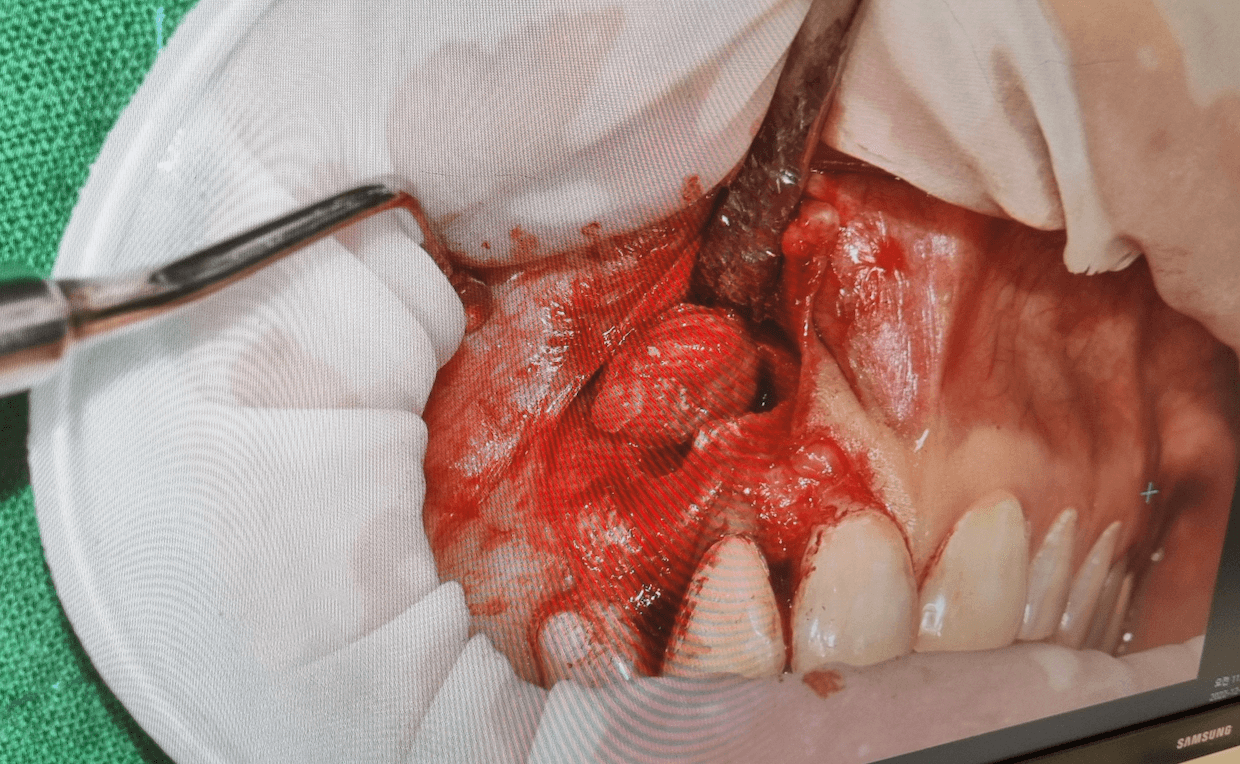

개인저긍로 치근단절제술이 임플란트를 해넣을때보다 2배정도 더 통증이 심했다고 생각을 합니다. 저같은 경우 염증이 뼈를 많이 녹였기 때문에 수술범위가 커서 그런지 수술후 마취가 풀리니 임플란트 해넣을때 보다 통증이 더 심했습니다.

임플란트할때도 뼈이식을 했는데, 치근단절제술은 특히 앞니 잇몸쪽을 절개해서 뼈를 이식하고 염증을 제거해석 그런지 몰라도 다시는 하고 싶지 않은 좋지 않은 통증을 느꼈습니다. 위 사진을 보시면 제법 아파 보이는데, 그렇게 못참을 만큼 아픈건 아니지만 임플란트 해넣는것 보다는 통증이 아프다고 말하고 싶네요.

치근단절제술 범위에 따라 통증은 다를수 있습니다.